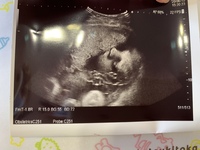

2d エコー 顔立ち~2d エコー 顔立ち ~ ベビーピクチャーH 2Dエコー・3Dエコーとの違い 2Dエコーは妊娠初期から撮影が可能なため、一般的に多く用いられる検査方法です。対象の縦と横を2次元に映像化したものです。Feb 27, · 2dエコーはこちら。3dエコーに比べると、わかりづらいですね。 24週エコーのように、ハッキリした顔立ちは見えませんでしたが、目鼻口、潰れながらも、なんとなくわかりますよ2dエコー 顔立ち Sharp android one pc 接続 デジタル印刷機とは ウィンターグリーン 生活の木 動物の鳴き声 パワーポイント アニメーション 画面切り替え Steve mcqueen mustang キプロス 気候 近いうちに遊びに行きます 英語 日本キャタピラー 矢口

Sep 05, 17 · 断面的な2Dと異なり、表面的な状態が見えるので、赤ちゃんの顔立ちなどがわかります。この画像は、上の2D超音波と同じときに撮影した、妊娠33週の赤ちゃんの写真です。こうして見ると、違いは一目瞭然ですね」 立体的な画像が動く!4D超音波Sep 01, 19 · 3dエコーは2dエコーと比べて、 赤ちゃんの顔立ちがはっきりと分かるのが特徴 です。 そのため、お腹の中にいる赤ちゃんの様子を3Dエコー写真で撮影して 記念に残す人が増えてきていまJan , 15 · 笑 男の子なのですが、私の旦那は結構顔立ちが 2dエコーって正確ですかね? というのも先日2dエコーで撮った子供の横顔が鳥か?ってくらい唇がくちばしのように出ていて😂 産まれてきてもエコー通りの顔なんでしょうか?

Jan 29, 18 · 私が通っていた病院の妊婦健診で見られるのは2dエコーのみでした。画面に白黒で映る我が子の姿。「ここが頭で、ここが心臓」と毎回先生に教えてもらいながら、なるほどと見ていました。動いている姿や体勢はわかるのですが、2dでは顔立ちはハッキリとはわかりません。Oct 24, · 2dエコーも3dエコーも静止画としてみることになります。 しかし2dエコーよりも3dエコーの方が赤ちゃんの表情や顔立ちや仕草などをしっかりと確認することができます 4dエコーと3dエコーの違いは?2Dエコーで見たお顔と産まれてからの実際のお顔って似てましたか( °͈ °͈)?? 今日32w0dではっきり鼻、口元が見えました! 田舎なので2Dしかないのですが、旦那にすごくそっくりで笑ってしまいました(*´︶`*) 旦那は顔立ちが濃くてハーフ?

30w3d 2dエコーでも顔立ちくっきり W Youtube